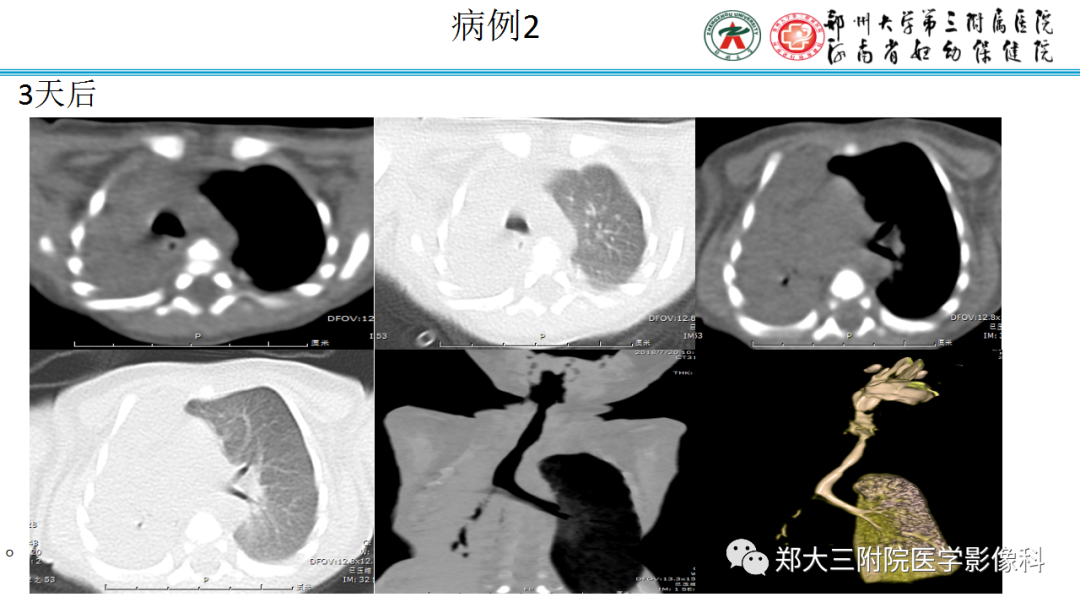

肺隔离症:易误诊为肺癌的占位性病变,肺穿刺禁忌!

肺隔离症:易误诊为肺癌的占位性病变,肺穿刺禁忌!  肺段与肺内管道应用解剖

肺段与肺内管道应用解剖  肺转移瘤的十种不典型CT表现

肺转移瘤的十种不典型CT表现  肺内淋巴结的CT表现特点及与病理对照

肺内淋巴结的CT表现特点及与病理对照  肺实变与肺不张的CT鉴别诊断

肺实变与肺不张的CT鉴别诊断  新冠肺炎典型影像学诊断与鉴别诊断

新冠肺炎典型影像学诊断与鉴别诊断  肺部分叶和分段影像解剖